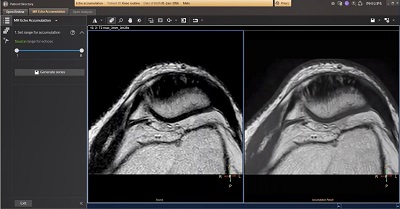

Echo Accumulation

Optimizing image contrasts for multi-echo MR data

MR Echo Accumulation used to perform pixelwise echo accumulations for imaging series with multiple echoes. MR Echo Accumulation enables the calculation of new images based on the selected sum of echo times of series with multiple echoes. The processing provides interactive update of the results.

• Provides the ability to define the accumulation range using an interactive slider.